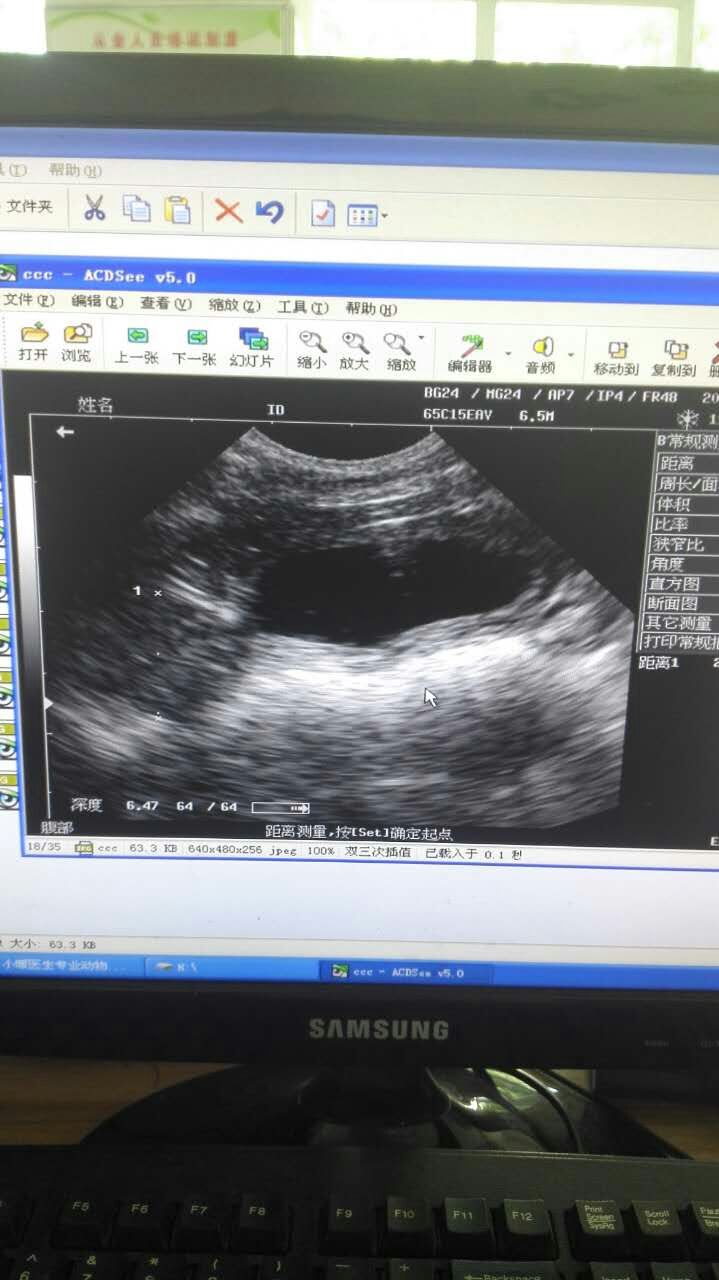

比熊犬,丑丑,雄性,3岁多。2016年5月16日,主人因丑丑尿血带来检查,检查后发现膀胱粘膜增厚,前列腺增大、囊肿。保守治疗两天后,未见明显好转,与主人沟通后,采取B超引导穿刺前列腺囊肿,抽取囊液,并行去势术,术后常规消炎7天。半月后复查,B超未探及囊肿,前列腺萎缩。小便正常,食欲精神正常。